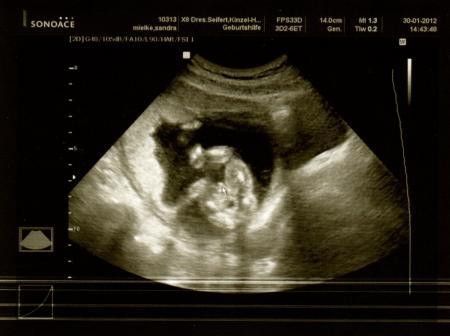

das sieht ganz nach nem Jungen aus ;-) schau mal, dass ist mein Outing Jungenfoto und das ist 100 %ig. Naja und unser Gefühl hat auch Mädel gesagt, wir haben also auch erstmal den großen Bruder *grins* - musste bei deinem Posting total lachen! Liebe Grüße aus dem Junibus

Bild zu